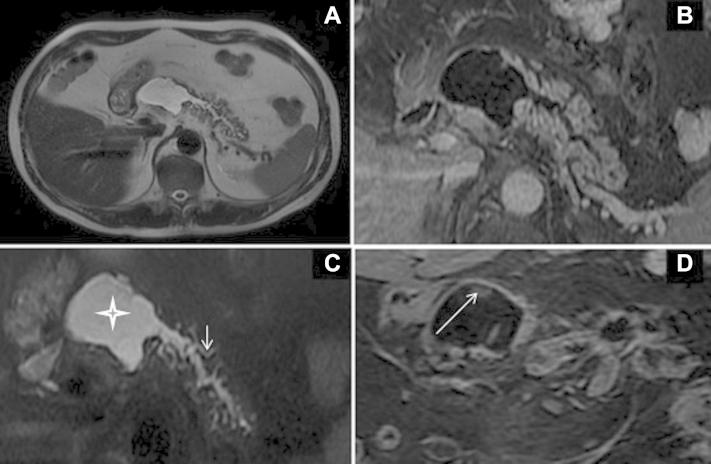

Intraductal papillary mucinous neoplasia (IPMN) is one of the cystic neoplasias of the pancreas. The imaging findings provide that these tumors are differentiated from the other cystic lesions of the pancreas, especially from the chronic pancreatitis, where the treatment protocol is completely different. Therefore, the correct diagnosis and classification of the IPMN ensures that the patient receives the correct approach and the appropriate surgery, if necessary. The purpose of this study is to emphasize the imaging findings of the different types of the IPMN and the changes in the management protocol of the patients according to these radiological findings.